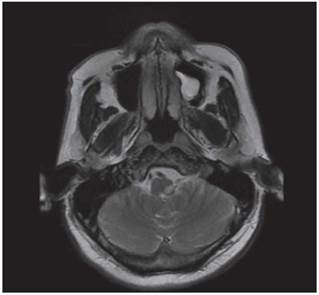

<p>Los estudios de hemograma, nitrógeno ureico, creatinina, glucemia y electrolitos se encontraron dentro de los rangos normales, el perfil lipídico mostró: colesterol total 160 mg/dl, colesterol HDL 50 mg/dl, colesterol LDL 89,8 mg/dl, triglicéridos 101 mg/dl. La tomografia de cráneo simple no mostró sangrado ni signos de isquemia. Se realizó una resonancia magnética cerebral simple que permitió evidenciar en las secuencias de T2 y FLAIR <italic>(Fluid Attenuation Inversion Recovery)</italic> una zona de hiperintensidad de señal a nivel del bulbo raquídeo en la región dorso-lateral caudal izquierda que es hipointensa en T1 (<xref ref-type="fig" rid="f1">figuras 1</xref>,<xref ref-type="fig" rid="f2">2</xref>,<xref ref-type="fig" rid="f3">3</xref>,<xref ref-type="fig" rid="f4">4</xref>). En la secuencia de difusión se observa restricción de la misma en la zona descrita con fenómeno de pseudonormalización al igual que en el mapa ADC <italic>(Apparent Coefficient Diffusion}</italic> (<xref ref-type="fig" rid="f5">figuras 5</xref>,<xref ref-type="fig" rid="f6">6</xref>). Los anteriores hallazgos se interpretaron como compatibles con un infarto bulbar lateral izquierdo.</p>

<p>El paciente se caracterizó por tener principalmente dis-fagia, disfonía, vértigo, ataxia y hemiparesia ipsilateral, las cuales rápidamente mejoraron, siendo llamativo la ausencia de nistagmo el cual se reporta en una incidencia importante. El estudio por resonancia magnética se logró realizar 1 semana posterior al inicio de los síntomas, lo cual generó la limitante de observar pseudo-normalización en la secuencia DWI (Diffusion Weighted Imaging) y por ende ausencia de una clara restricción de la difusión. En el T2 corte coronal se puede ver extensión hacia zonas caudales de la unión bul-bomedular, lo cual explicaría por qué presentó compromiso del tracto cortico-espinal siendo la primera causa, la lesión de las fibras ya decusadas provenientes del hemisferio contrala-teral ya sea por isquemia o por efecto de masa por el edema adyacente, este hallazgo se correlaciona con lo mayormente reportado en otras publicaciones. Un elemento importante en el paciente fue el inicio súbito de los síntomas posterior a realizar una rotación brusca del cuello con dolor cervical asociado, lo cual debe ubicar al clínico en un contexto cuya principal etiología a estudiar sea la disección cervical dada además la ausencia de factores de riesgo cardiovasculares y la edad cercana a los 50 años, sin embargo, en una angiografía convencional tomada 3 semanas después, no se evidenció esta etiología según lo informado por radiología. A pesar del compromiso motor, no todos los pacientes que cursan con síndrome de Opalski tienen una afectación marcada de la funcionalidad e independencia <xref ref-type="bibr" rid="B17"><sup>17</sup></xref> y la debilidad evidenciada es leve y transitoria permitiendo su recuperación hasta el 100 % previo, como se observó en este caso. Por otro lado, es importante evitar complicaciones tempranas como la broncoaspiración y neumonitis secundaria y, por ende, se hace imperativo plantear desde el ingreso de estos pacientes una vía alterna de alimentación a través de sonda naso u orogástrica o gastrostomía mientras se lleva a cabo el proceso de rehabilitación de la disfagia de forma paralela.</p>